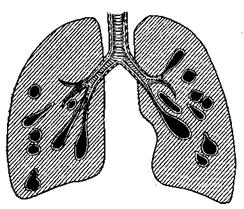

<Бронхоэктазы >< >< ><- >< ><расширение >< ><стенок >< ><бронхов >< >< ><с >< ><образованием ><полостей ><в >< ><виде ><мешков >< ><или ><цилиндров.

<Бронхоэктазы ><могут ><быть ><множественными ><и ><различного ><характера.>

<Они ><превращаются ><в ><большие ><полости, ><в ><которых ><скапливается> <мокрота ><и ><гной. >< >< ><Бронхоэктазы ><являются ><постоянными ><очагами>

<инфекции ><и ><интоксикации.

Рис. 11. Множественные бронхоэктазы